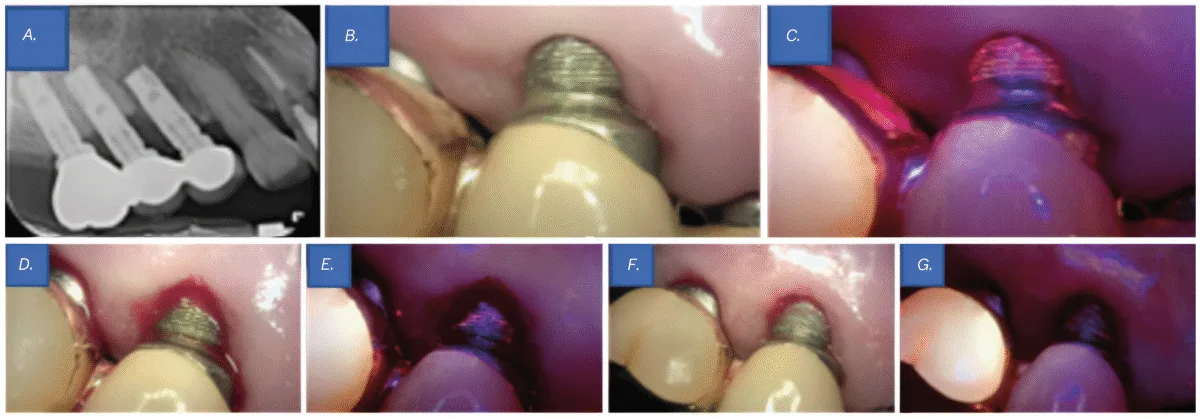

Scientific examination revealed probing depths of 5–6 mm round implant Nos. 4 and 5, with thread publicity at implant No. 5 above the gingival margin. Radiographic examination revealed bone loss round implant Nos. 4 and 5, resulting in a prognosis of peri-implantitis (Determine 3A). Though no vital biofilm accumulation was seen to the bare eye (Determine 3B), analysis utilizing QLF clearly detected biofilm that was not observable beneath typical visible inspection (Determine 3C). Contemplating the affected person’s osteoporosis and the truth that solely 4 months had handed since her final denosumab (Prolia®) injection, flap surgical procedure was not carried out. As a substitute, curettage was chosen because the remedy method.

For biofilm elimination, cleaning was carried out utilizing an ultrasonic scaler (Megagen, Seoul, South Korea), a curette, and a microbrush. After mechanical debridement, QLF imaging was performed once more to match pre- and post-treatment findings. Whereas no biofilm was seen to the bare eye (Determine 3D), QLF revealed residual biofilm on the implant threads (Determine 3E). Extra debridement was carried out, adopted by one other spherical of medical and QLF imaging for affirmation (Figures 3F-3G). This course of enabled a extra thorough analysis of biofilm elimination and served as a visible help for affected person schooling on oral hygiene. Focused brushing instruction (TBI) was additionally offered.

The realm was then rinsed with 0.2% chlorhexidine, and a pair of% minocycline ointment (Periocline®, Sunstar, Osaka, Japan) was topically utilized to the peri-implant lesion for irritation management.

On the 2-week follow-up, peri-implant irritation had considerably decreased, and the affected person reported reduction from discomfort. On the 6-month follow-up, solely delicate irritation was noticed within the surrounding space, however the affected person remained symptom-free, and the peri-implant tissues have been properly maintained.